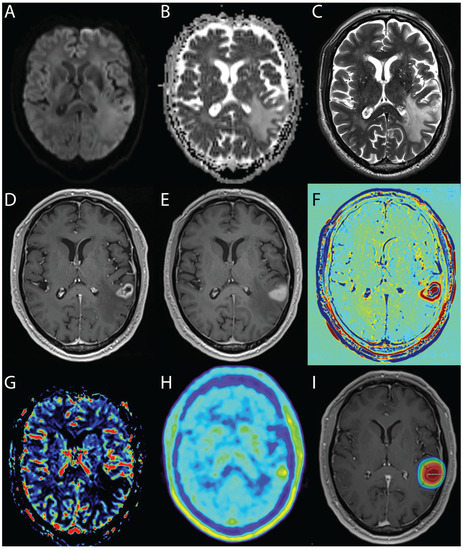

4.1.3. Diffusion-Weighted MRI

4.1.4. Perfusion-Weighted Imaging—Glioma

4.1.5. Perfusion-Weighted Imaging—Metastases

4.3. Nuclear Medicine—PET

4.3.1. PET Tracers

4.3.2. 18F-FET—PET

- Asao, C.; Korogi, Y.; Kitajima, M.; Hirai, T.; Baba, Y.; Makino, K.; Kochi, M.; Morishita, S.; Yamashita, Y. Diffusion-Weighted Imaging of Radiation-Induced Brain Injury for Differentiation from Tumor Recurrence. AJNR Am. J. Neuroradiol. 2005, 26, 1455–1460. [Google Scholar]

- Hein, P.A.; Eskey, C.J.; Dunn, J.F.; Hug, E.B. Diffusion-Weighted Imaging in the Follow-up of Treated High-Grade Gliomas: Tumor Recurrence Versus Radiation Injury. AJNR Am. J. Neuroradiol. 2004, 25, 201–209. [Google Scholar] [PubMed]

- Castillo, M.; Smith, J.K.; Kwock, L.; Wilber, K. Apparent Diffusion Coefficients in the Evaluation of High-Grade Cerebral Gliomas. AJNR Am. J. Neuroradiol. 2001, 22, 60–64. [Google Scholar] [PubMed]

- Chan, Y.L.; Yeung, D.K.; Leung, S.F.; Chan, P.N. Diffusion-Weighted Magnetic Resonance Imaging in Radiation-Induced Cerebral Necrosis. Apparent Diffusion Coefficient in Lesion Components. J. Comput. Assist. Tomogr. 2003, 27, 674–680. [Google Scholar] [CrossRef] [PubMed]

- Sundgren, P.C.; Fan, X.; Weybright, P.; Welsh, R.C.; Carlos, R.C.; Petrou, M.; McKeever, P.E.; Chenevert, T.L. Differentiation of Recurrent Brain Tumor Versus Radiation Injury Using Diffusion Tensor Imaging in Patients with New Contrast-Enhancing Lesions. Magn. Reson. Imaging 2006, 24, 1131–1142. [Google Scholar] [CrossRef]

- Zeng, Q.S.; Li, C.F.; Liu, H.; Zhen, J.H.; Feng, D.C. Distinction between Recurrent Glioma and Radiation Injury Using Magnetic Resonance Spectroscopy in Combination with Diffusion-Weighted Imaging. Int. J. Radiat. Oncol. Biol. Phys. 2007, 68, 151–158. [Google Scholar] [CrossRef]

- Bobek-Billewicz, B.; Stasik-Pres, G.; Majchrzak, H.; Zarudzki, L. Differentiation between Brain Tumor Recurrence and Radiation Injury Using Perfusion, Diffusion-Weighted Imaging and Mr Spectroscopy. Folia Neuropathol. 2010, 48, 81–92. [Google Scholar]